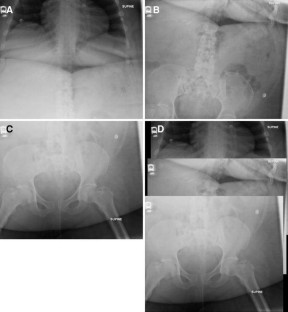

Fig. 1